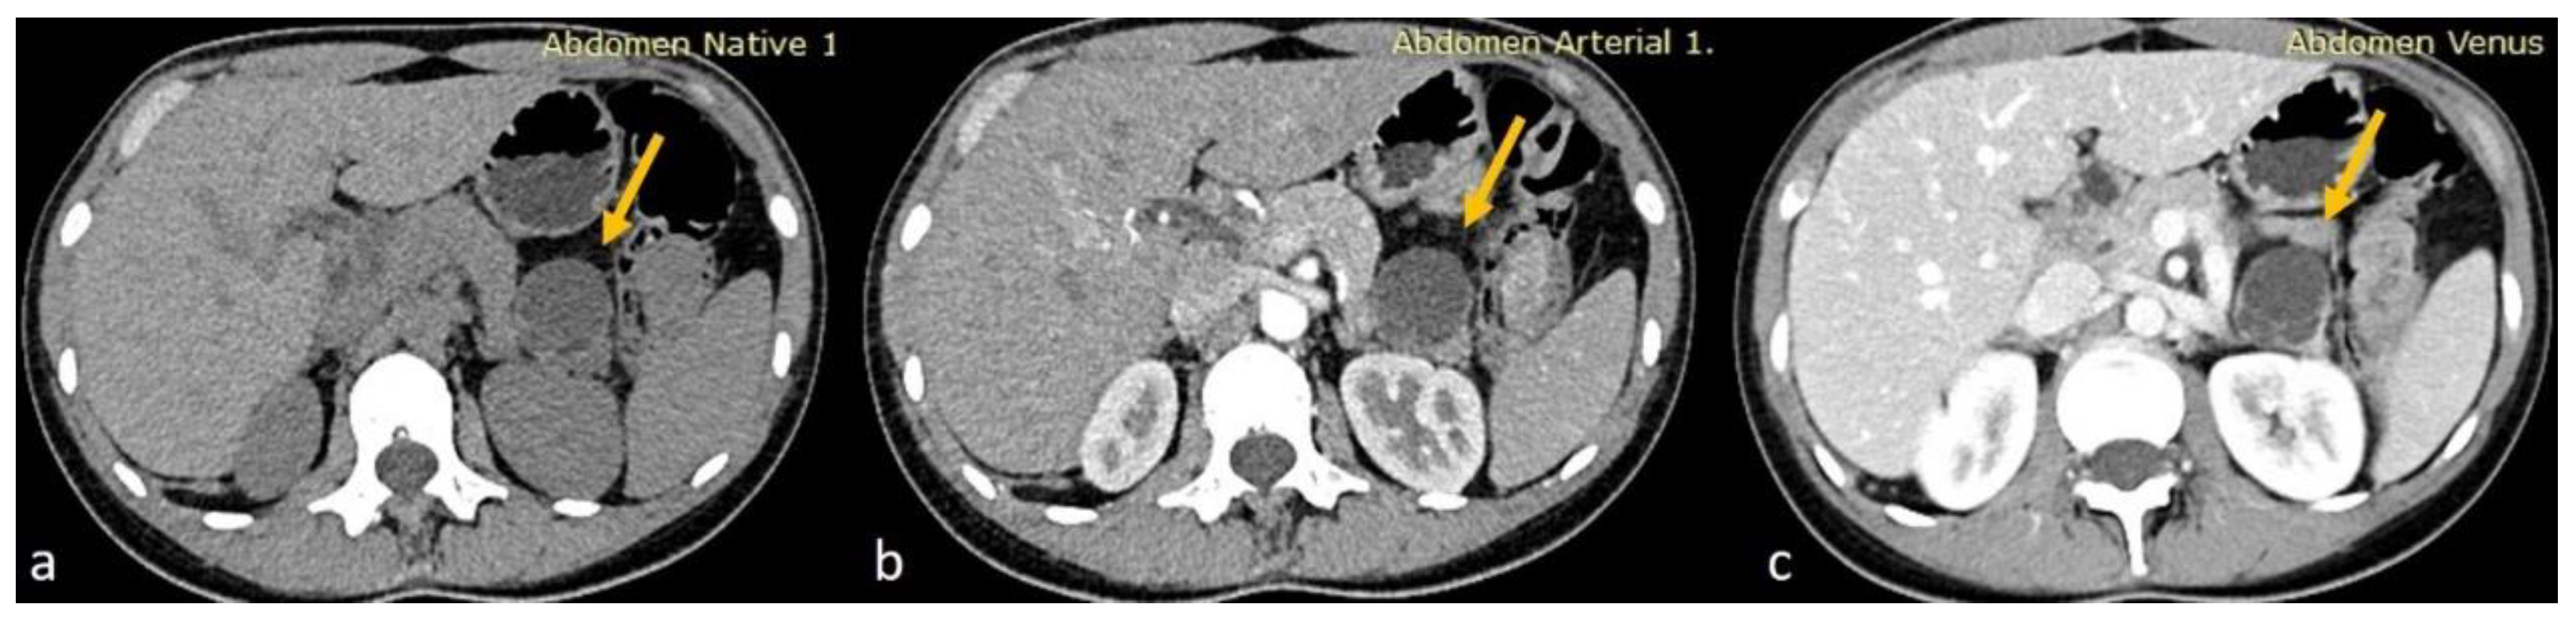

Given the moderate severity of her pain, a CT scan of the upper and lower abdomen, along with the retroperitoneal space, was performed using a polytomous technique in both arterial and venous phases after the rapid administration of contrast. The scan revealed a 3.8 cm hypodense cystic lesion located in the tail of the pancreas. The lesion exerted pressure on the adjacent pancreatic tissue but showed no dilation of the main pancreatic duct. It had a smooth, mildly enhanced wall with internal septations, without any calcifications or solid components. A 9 mm hemangioma was also observed in the liver, and no other significant abnormalities were found in the kidneys, adrenal glands, uterus, or ovaries. The findings were consistent with a mucinous cystadenoma as the primary diagnosis, with other possible differentials including a pancreatic neuroendocrine tumor (PNET), simple cyst, or lymphangioma (Figure 1).

Figure 1.

(a) Axial non-enhanced CT of the abdomen showing a cystic lesion at the tail of the pancreas with thin septations. No wall calcifications appreciated (yellow arrows). (b,c) Axial contrast-enhanced CT sections in arterial and venous phases, respectively, showing minimal wall enhancement of the cyst wall and the septations of the pancreatic cyst with no internal solid component.